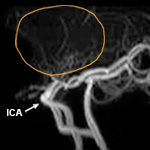

- Moyamoya disease

Moyamoya disease is caused by blocked arteries at the base of the brain. The name "moyamoya" means "puff of smoke" in Japanese and describes the appearance of tiny vessels that form to compensate for the blockage. As the normal blood vessels narrow and become blocked, a person may suffer a stroke. No medication can stop or reverse the progression of moyamoya disease. Treatment focuses on reducing the risk of stroke and restoring blood flow to the brain.